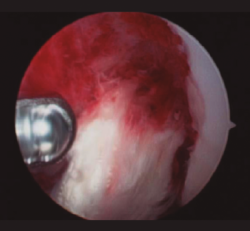

Figura 3. Imagen intraoperatoria artroscópica que muestra el abundante tejido esfacelar en un caso de artritis séptica de rodilla.

Cuando la infección ya se ha producido, el tratamiento de elección debe ser realizado tan pronto como sea posible y en cuanto haya sospecha clínica de infección, refrendada o no por los resultados de las pruebas complementarias, los cuales no justifican una demora en la actuación. Este tratamiento consiste en asociar un desbridamiento artroscópico agresivo al inicio del tratamiento antibiótico(4,5,9). Durante el desbridamiento artroscópico es obligatorio recoger muestras para el cultivo antes de la administración de antibióticos, y ambas terapias deben realizarse lo antes posible. La artroscopia debe incluir lavado extensivo con suero, desbridamiento de tejido desvitalizado, eliminación de fibrina, coágulos y sinovectomía (Figuras 3 y 4).